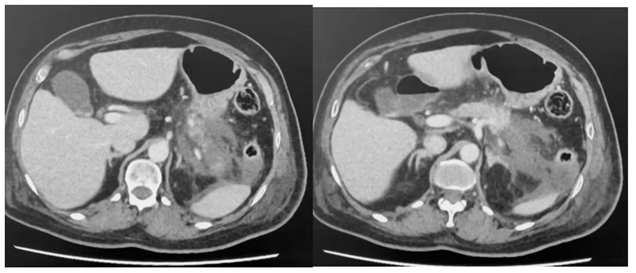

Paciente com pancreatite aguda que necessitou durante 36 h de droga vasoativa no início de tratamento,

realizou a tomografia com contraste endovenoso no quinto dia de internação, conforme abaixo.

De acordo com as informações e tomografia acima, assinale a alternativa correta.